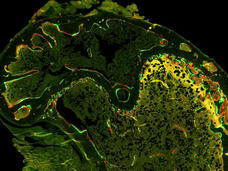

New Approach Uses Much Less Tissue to Analyze Tumor Proteins and Genes

Researchers have developed a “microscaled” approach to analyze the proteins and genetic changes (proteogenomics) of a tumor that uses tissue from a core needle biopsy. The analyses can provide important information that may help guide treatment.